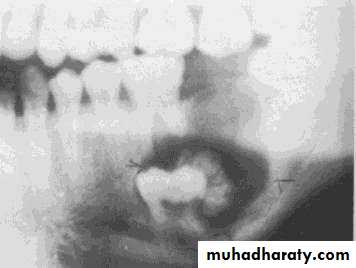

• Calcifying epithelial odontogenic tumor

• Radiograph:

• The lesion appears as radiolucent area with poorly defined margin with fine flecks of radio-opacities (due to calcification).• Impacted tooth and flicks of calcification